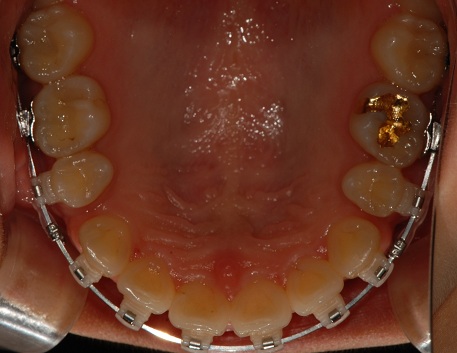

하악사진